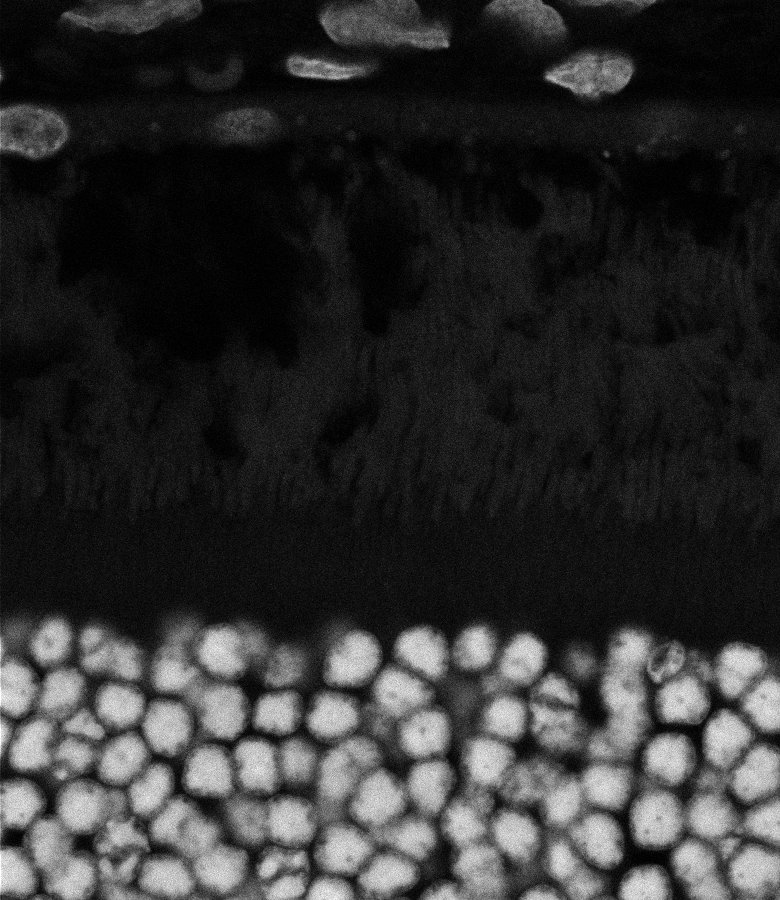

Healthy Retina

Unhealthy Retina

Healthy Choroid

Unhealthy Choroid